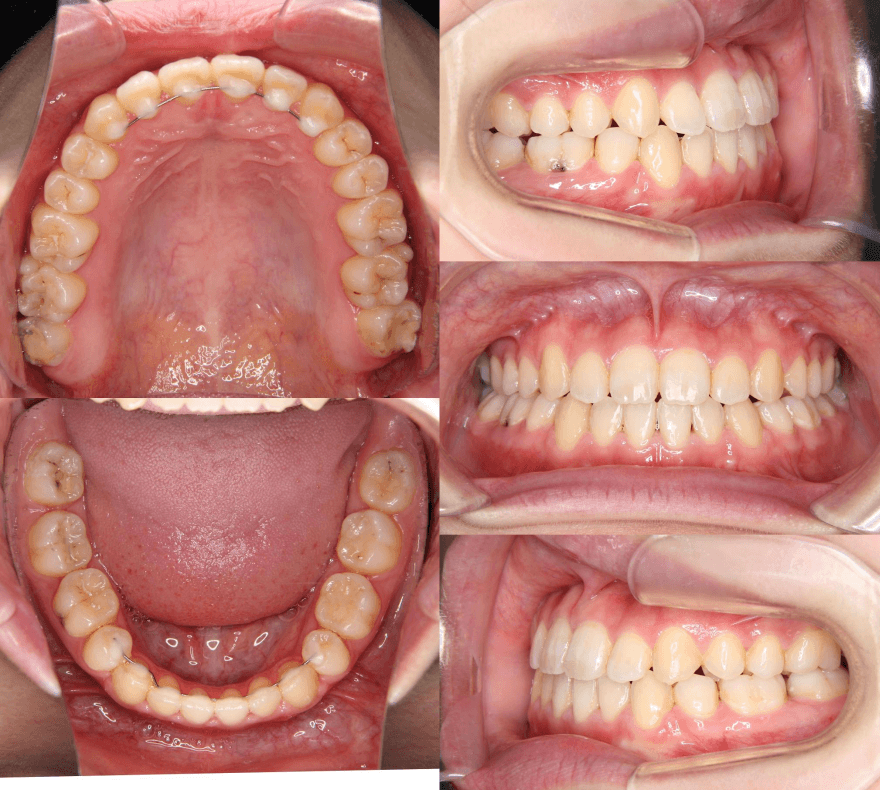

| 年齢・性別 | 15歳の女性 |

|---|---|

| 主訴 | 咬み合わせが逆であること(反対咬合)を気にされて来院された15歳7か月の女性。見た目や機能面の改善を希望されていました。 |

| 治療期間・回数 | 4年4ヶ月・28回 |

| 費用 | 900,000円 |